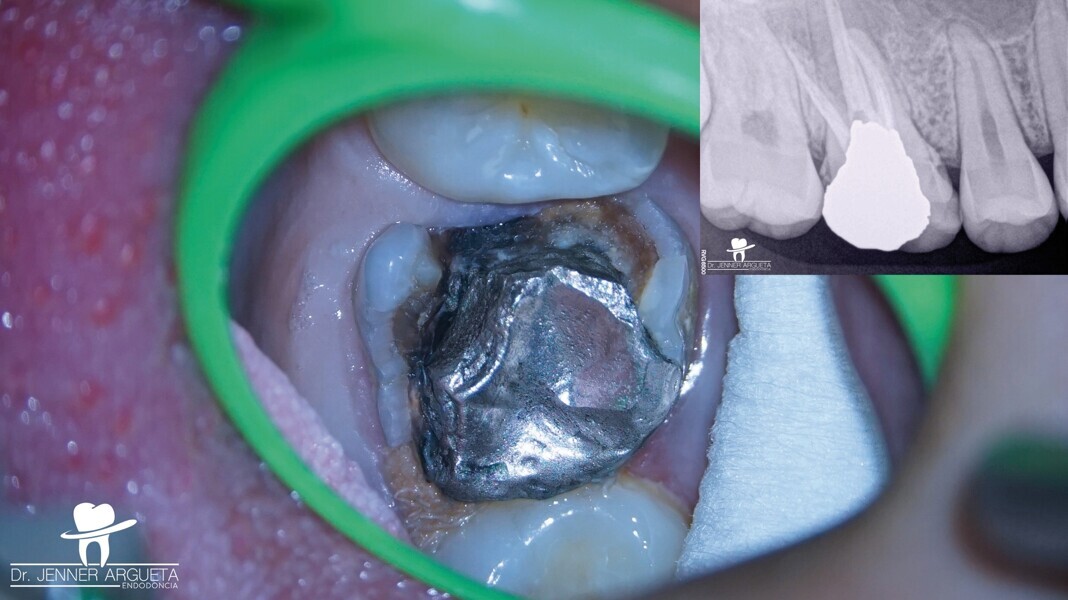

Une patiente de 16 ans a consulté le cabinet pour une évaluation de sa première molaire droite supérieure (dent 16 – Fig. 1). L’orthodontiste qui nous l’avait adressée demandait que tout soit mis en œuvre pour sauver cette dent. Le diagnostic était une parodontite périapicale symptomatique ayant déjà fait l’objet d’un traitement, et un examen minutieux a exclu toute possibilité de restauration. Avec l’accord des parents et de la patiente, nous avons pris la décision d’extraire la dent 16 et de procéder à une transplantation autogène de la dent 18 dans ce site (Fig. 2), étant donné que l’orthodontiste avait déjà prévu l’extraction de cette dent 18 et l’équilibration de l’occlusion de la patiente à la fin du traitement orthodontique. Les dents n 16 et 18 ont été extraites de la manière la moins traumatique possible. Après un remodelage osseux mineur de l’alvéole à l’aide de fraises à basse vitesse, la troisième molaire a été transplantée dans l’alvéole receveuse (Fig. 3). Une contention flexible constituée d’un monofilament de nylon a été utilisée pour maintenir la dent en place (Fig. 4). Deux semaines plus tard, la contention a été retirée, laissant des tissus mous sains et asymptomatiques et une alvéole dans laquelle la dent était stable (Figs. 5a et b).

La patiente s’est présentée au cabinet huit mois plus tard avec des signes et des symptômes de nécrose pulpaire et d’abcès périapical aigu mis en évidence par une radioclarté. La zone rétromolaire était bien cicatrisée (Fig. 6). Dans des cas comme celui-ci, où la structure coronaire est encore intacte, il est conseillé de recourir aux nouvelles techniques endodontiques et d’adopter une approche conservatrice du traitement endocanalaire afin d’obtenir de meilleurs résultats. Le puits d’accès endodontique a été créé au moyen de fraises à haute vitesse et d’inserts ultrasoniques. Le protocole de nettoyage et de mise en forme a été réalisé à l’aide de canules et de limes flexibles en alliage à mémoire de forme contrôlée (Aurum Blue, Meta Biomed), dont les propriétés sont particulièrement importantes lors de la pénétration dans les canaux radiculaires par l’accès conservateur (Figs. 7a et b).